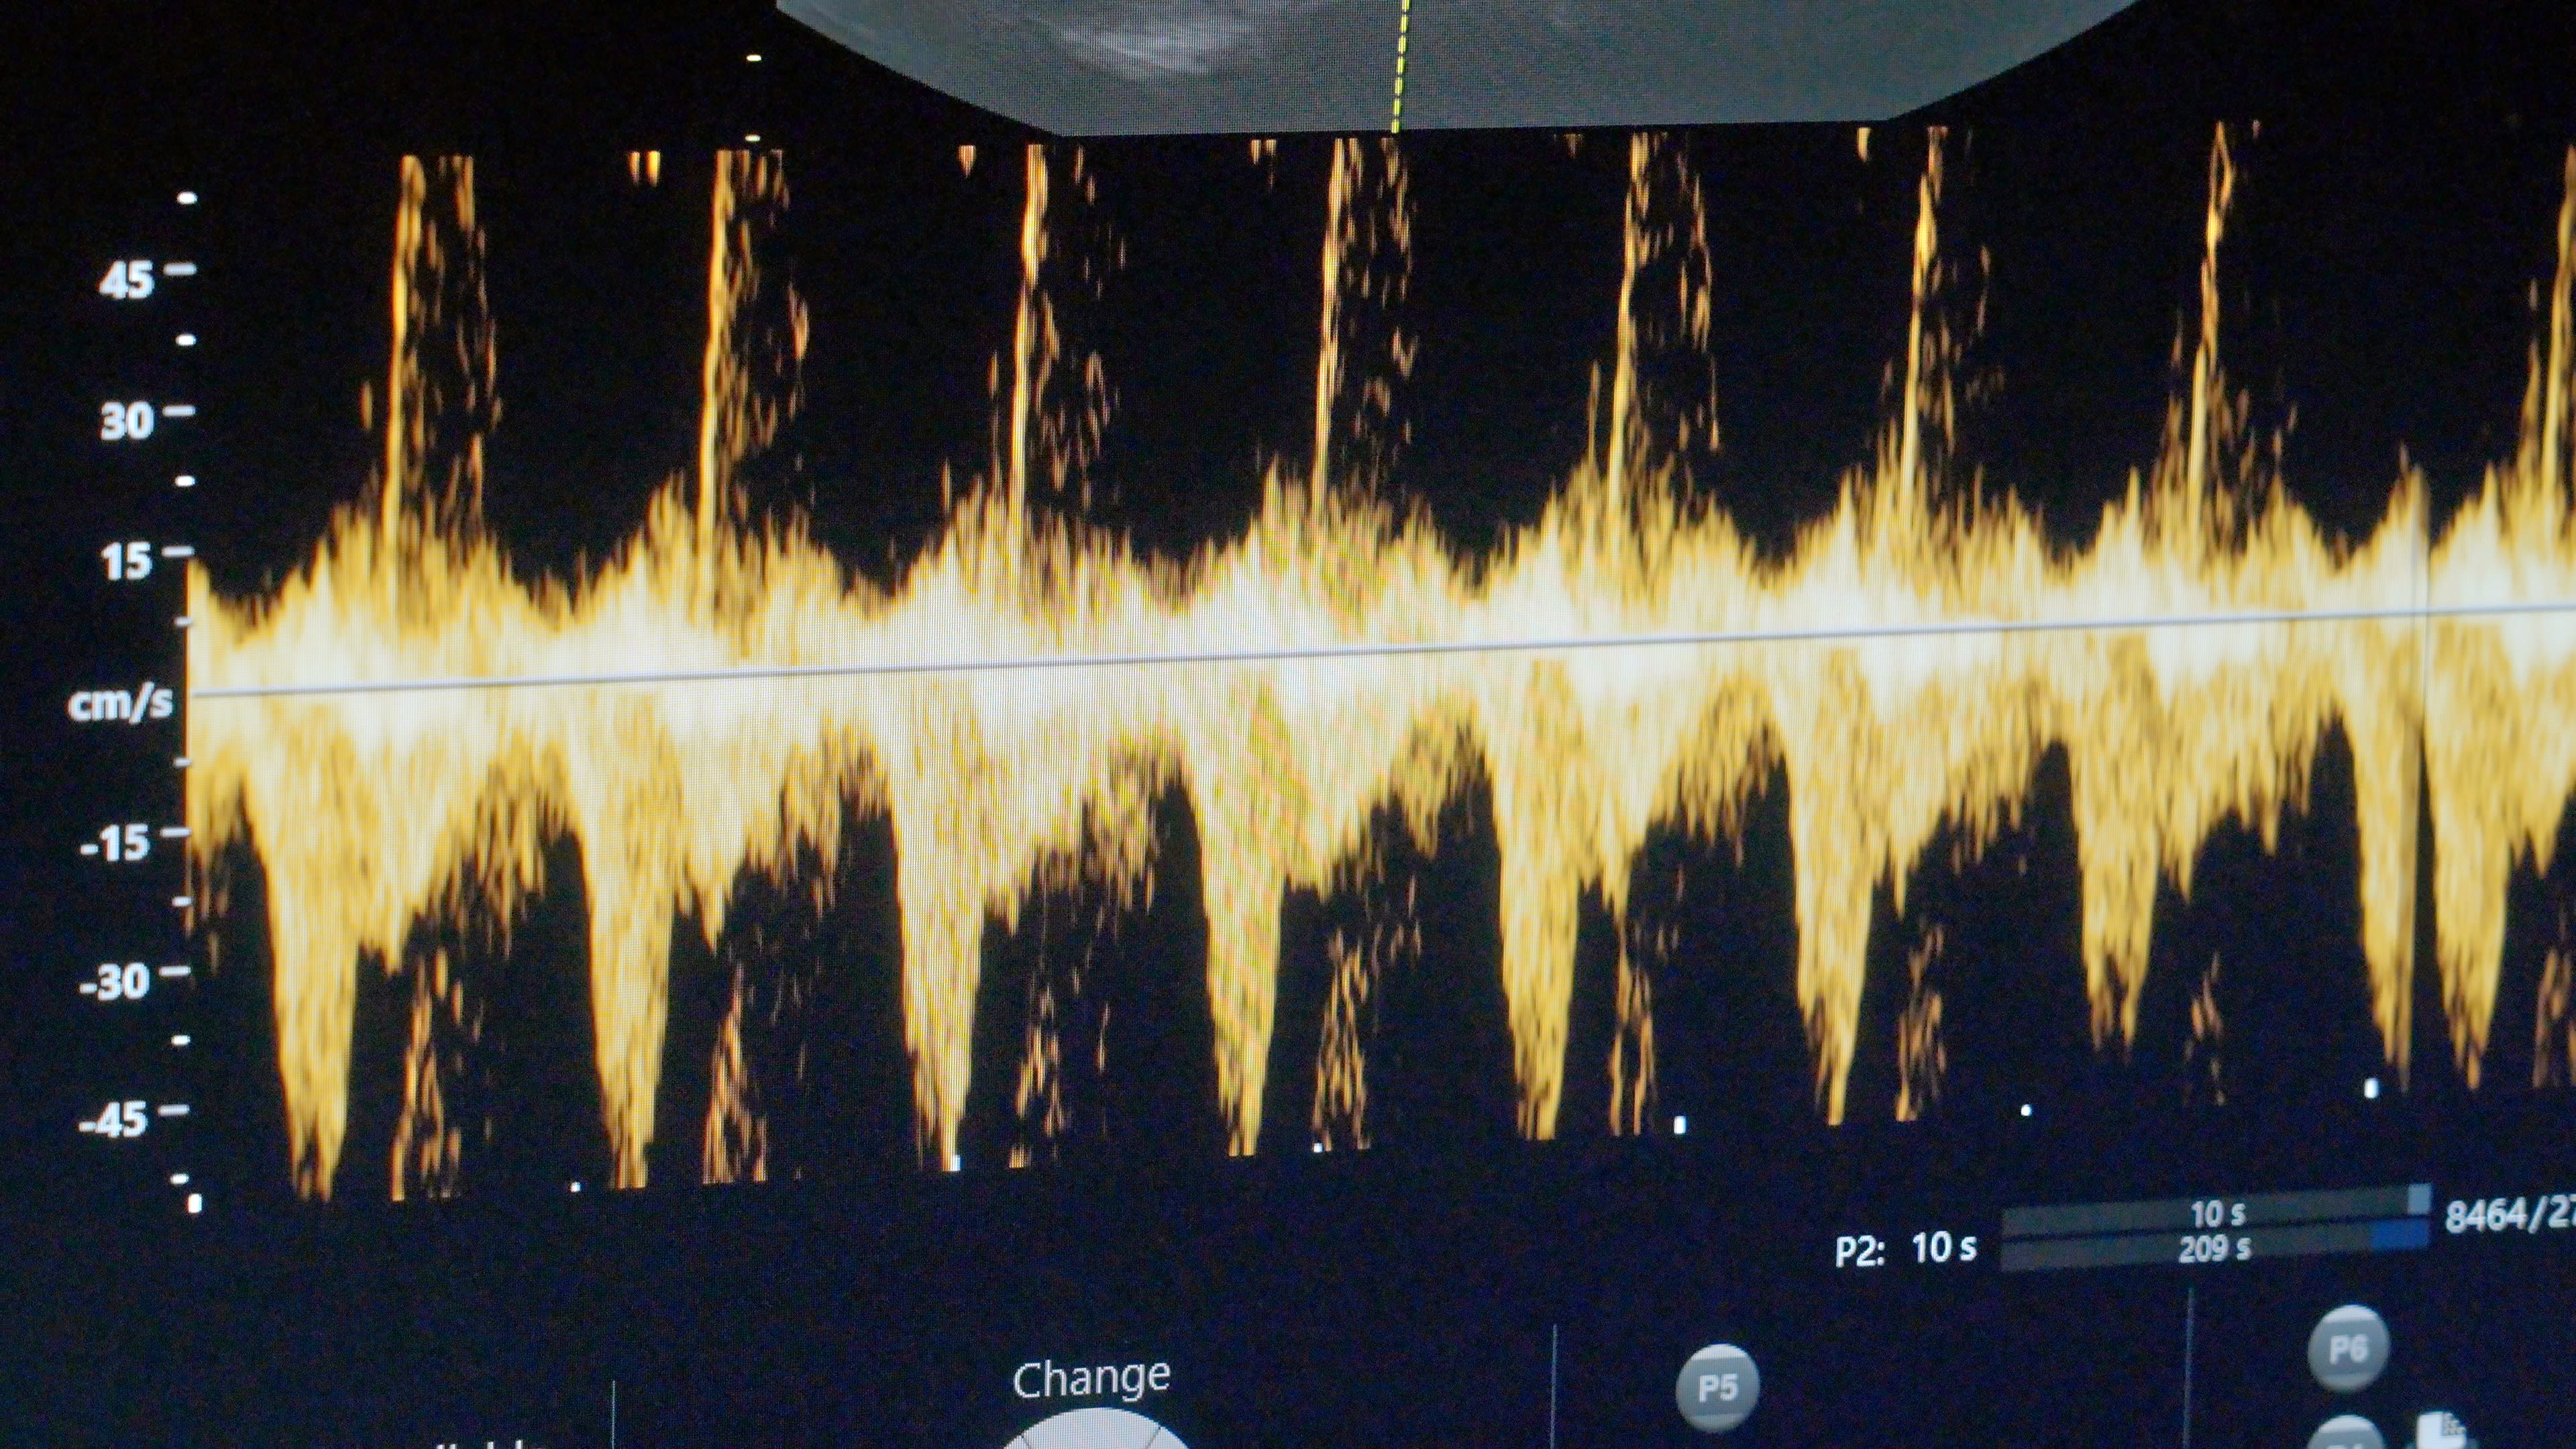

Fue en medio de la pandemia que la ucraniana Viktoria Huzova contrajo matrimonio. Ahora, a sus 28 años, la posibilidad de convertirse en madre está marcada por la invasión a gran escala de Rusia a Ucrania.

“El primer año no hubo pensamientos al respecto. Al contrario, debido al estrés, comencé a tener algunos problemas relacionados con el sistema reproductivo”, contó. Viktoria lo describe como el “síndrome de vida retrasada”, que se manifiesta al desear posponer decisiones o eventos importantes de la vida, hasta que mejoren las circunstancias.

No obstante las dificultades que la invasión rusa impone al pueblo ucraniano, algo cambió en la percepción de vida de ella y de su esposo.

“Entendimos que la guerra podía durar un año, dos años, podía durar diez años. No podemos influir en esto de ninguna manera y no podemos saber cuándo terminará” .

Así que el deseo de este matrimonio de convertirse en padres, fue más potente que las preocupaciones que les produce la guerra.

Viktoria habla con gratitud y esperanza: “La guerra puede continuar durante muchos años más, pero nuestra vida no termina ahí. Seguimos viviendo”.

Clínica Hryshchenko de Medicina Reproductiva

Hospital de Maternidad de Kyiv No. 3